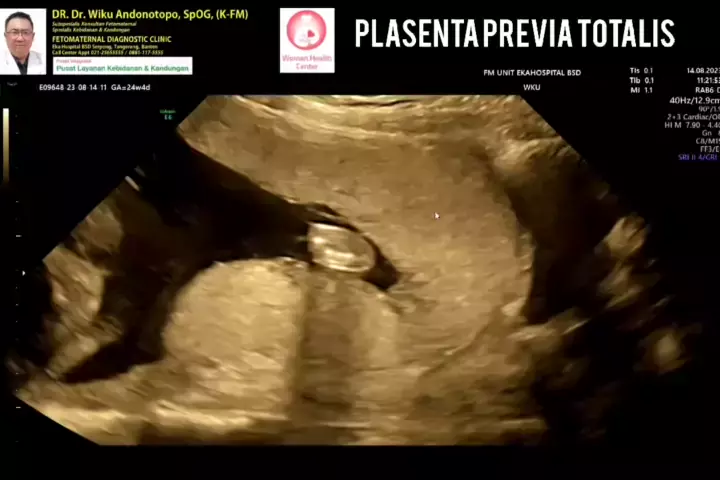

Plasenta Previa Totalis... #drwikuandonotopo #konsultanfetomaternalpontianak #fetomaternalpontianak #konsultanfetomaternalsemarang #usgfetomaternaltangerang #fetomaternalsemarang #usgfetomaternalbsd #ekahospitalbsd #fetomaternal #spog #polikandunganekahospitalbsd # #plasentaprevia #plasentapreviatotalis #placentaprevia المزيد